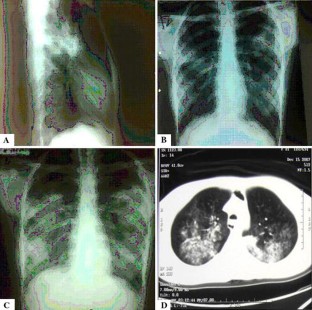

Fig. 1

Fig. 2

Fig. 3